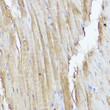

| Short Description | Rabbit polyclonal STAT2 (550-706) antibody for use in WB, IHC-P and ELISA in human, mouse and rat samples. Datasheet included with dilution recommendations, and related reagents. |

| Applications | WB/IHC-P/ELISA |

| Dilution Range | WB:1:500-1:1000IHC-P:1:50-1:200ELISA:Recommended starting concentration is 1 Mu g/mL. Please optimize the concentration based on your specific assay requirements. |